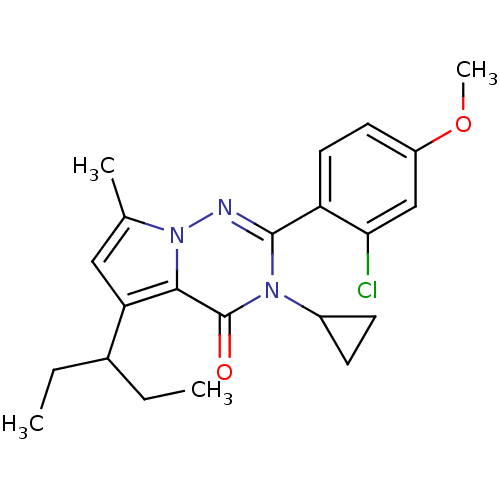

TargetCorticotropin-releasing factor receptor 1(Homo sapiens (Human))

Dupont Pharmaceuticals

Curated by ChEMBL

Dupont Pharmaceuticals

Curated by ChEMBL

Affinity DataEC50: 0.300nMAssay Description:Antagonist activity at human CRF1 receptor expressed in CHO-K1 cells assessed as CRF-stimulated cAMP accumulation by enzyme immunoassayMore data for this Ligand-Target Pair

Affinity DataEC50: 0.420nMAssay Description:Antagonist activity at CRF-R1 in mouse AtT-20 cells assessed as inhibition of human CRF induced cAMP accumulation after 30 mins by radioimmunoassayMore data for this Ligand-Target Pair

Affinity DataEC50: 0.440nMAssay Description:Antagonist activity at CRF-R1 in mouse AtT-20 cells assessed as inhibition of human CRF induced cAMP accumulation after 30 mins by radioimmunoassayMore data for this Ligand-Target Pair

Affinity DataEC50: 0.450nMAssay Description:Antagonist activity at CRF-R1 in mouse AtT-20 cells assessed as inhibition of human CRF induced cAMP accumulation after 30 mins by radioimmunoassayMore data for this Ligand-Target Pair